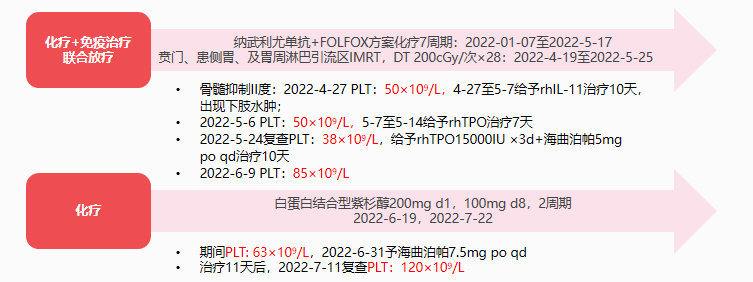

患者于2022-01-07至2022-5-17行FOLFOX方案(奥沙利铂+5-FU+亚叶酸钙)+纳武利尤单抗7周期,在第5周期后复查CT(2022-04-06 )提示贲门癌累及食管下段,较前(2022-02-24)略饱满,盆腔积液较前增多。考虑疗效欠佳,于2022-4-19至2022-5-25联合放射治疗(贲门、患侧胃、及胃周淋巴引流区IMRT,DT 200cGy/次×28)。

患者于2022-4-22开始第6周期化疗联合免疫治疗,并同步进行放疗。2022-4-25出现II度骨髓抑制,血小板75×109/L,予重组人白介素-11(rhIL-11)治疗10天,但血小板持续下降至45×109/L,且出现下肢水肿,遂改为重组人血小板生成素(rhTPO)治疗7天,血小板升高至90×109/L。在持续的抗肿瘤治疗下,患者再次出现CTIT(血小板38×109/L),给予rhTPO 15000IU皮下注射3天,联合海曲泊帕5mg 口服治疗10天,血小板维持稳定。

2022-06-13复查CT示伴腹膜后淋巴结转移、纵隔淋巴结转移,小网膜及肠系膜转移略加重,腹盆腔积液较前增多,考虑疾病进展,故更改治疗方案为白蛋白结合型紫杉醇200mg d1、100mg d8 2周期。

患者第1周期化疗结束后再次出现II度骨髓抑制,血小板降至63×109/L,予海曲泊帕7.5mg/天进行院外治疗,11天后患者返院,复查血常规升至120×109/L,顺利完成第2周期化疗。